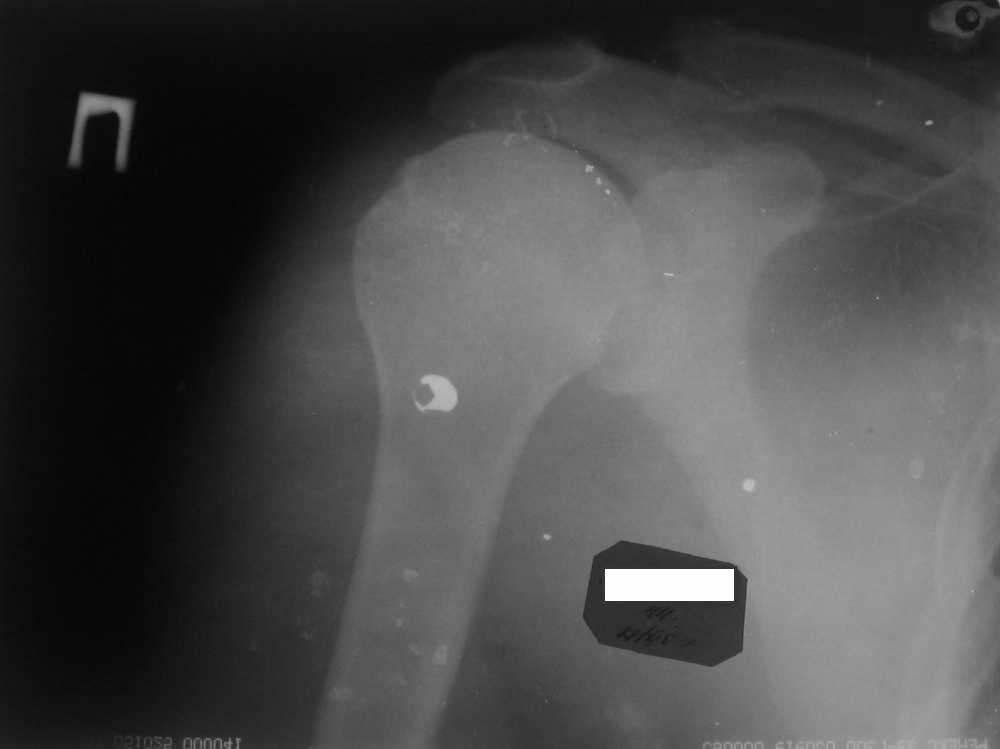

Мужчина, 45 лет. Профессионально занимается культуризмом. При жиме лёжа возникают резкие боли в левом ключично-акромиальном сочленении в течение 3 лет. В покое болей нет.

Похожая картина была и справа, однако удалось стабилизировать ситуацию с помощью консервативоного лечения.

Что, на Ваш взгляд, следует предпринять? Какие дополнительные исследования были бы полезны для определения тактики? Нет ли здесь показаний к декомпрессии подакромиального пространства? Если да, то что именно сделать?